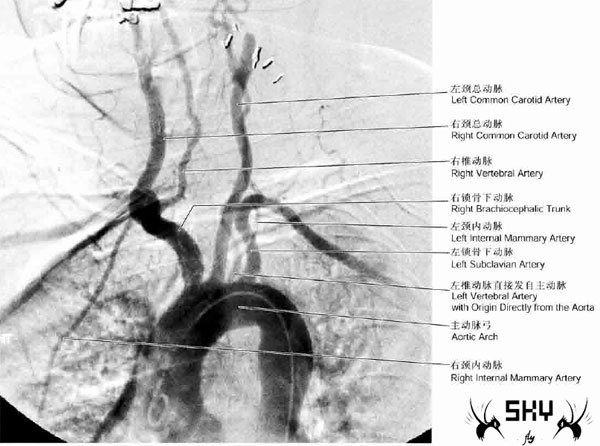

②左侧椎动脉在左颈总动脉和左锁骨下动脉之间,直接发自主动脉弓;如下图:

CA2